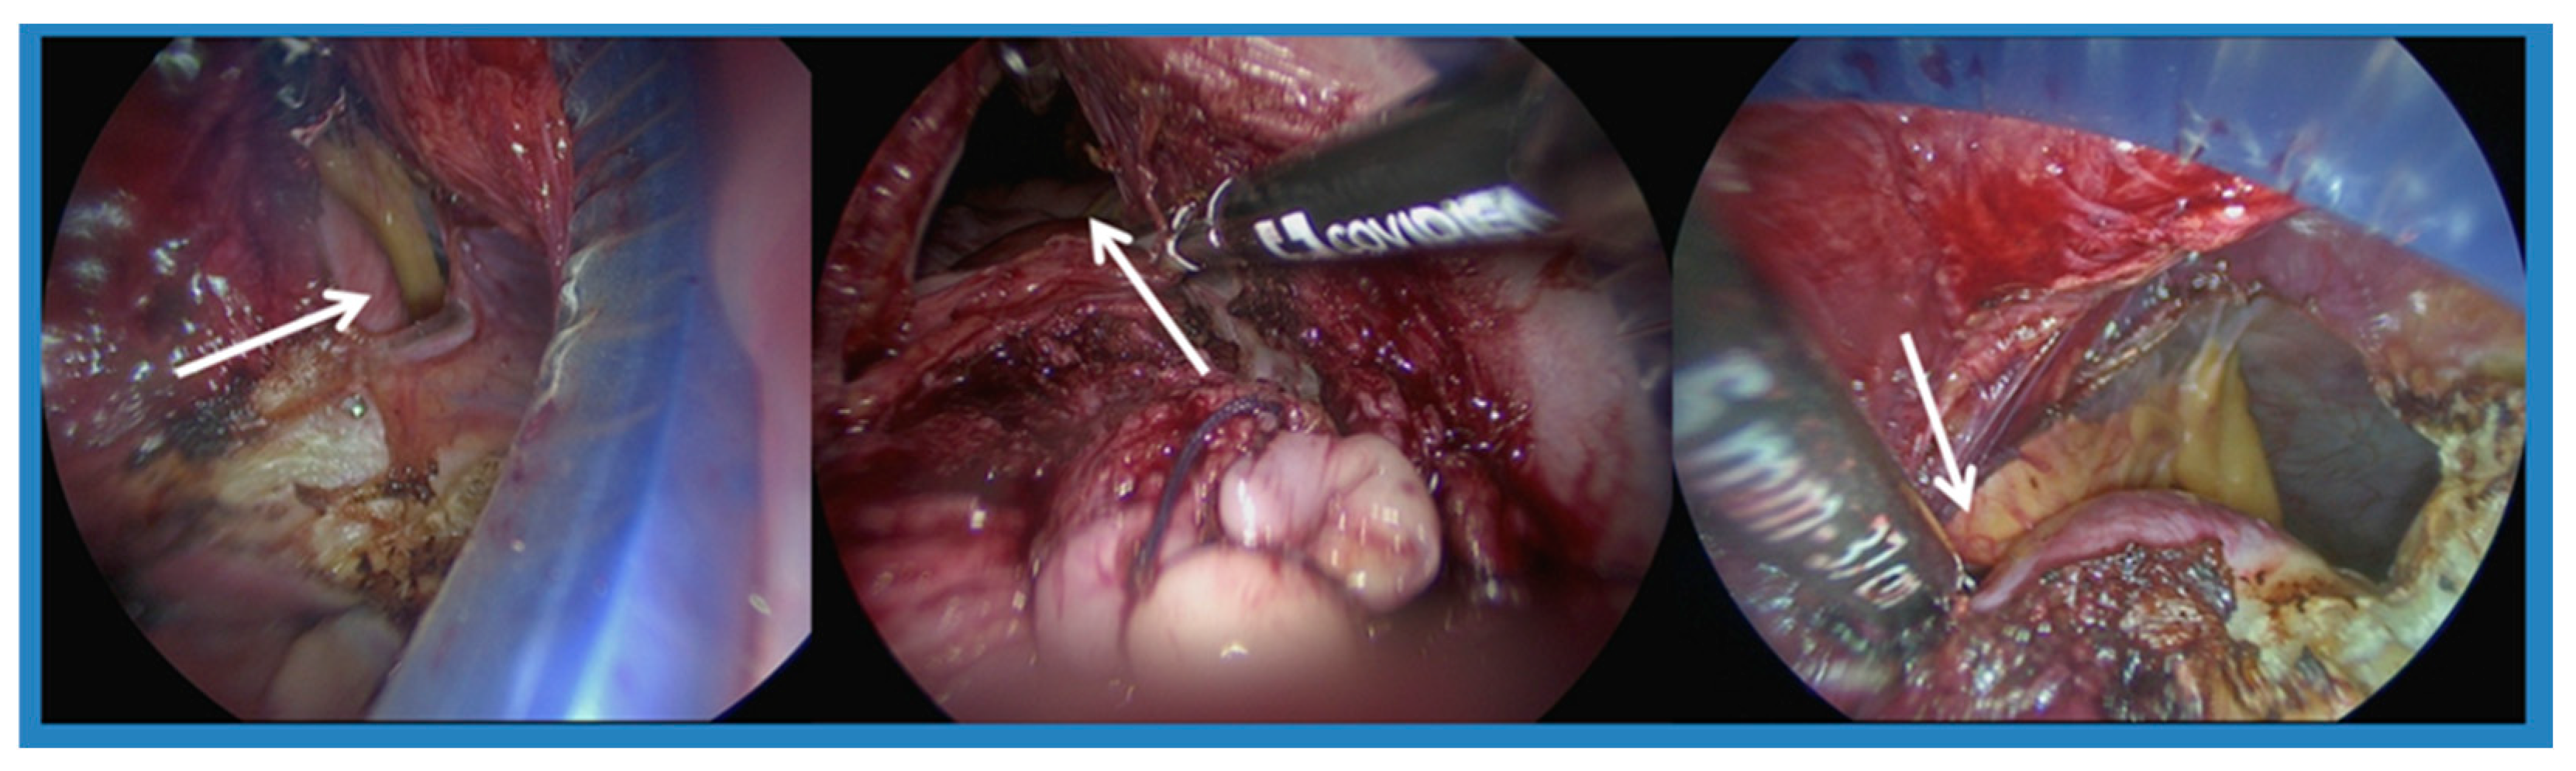

2.2. Surgical Technique